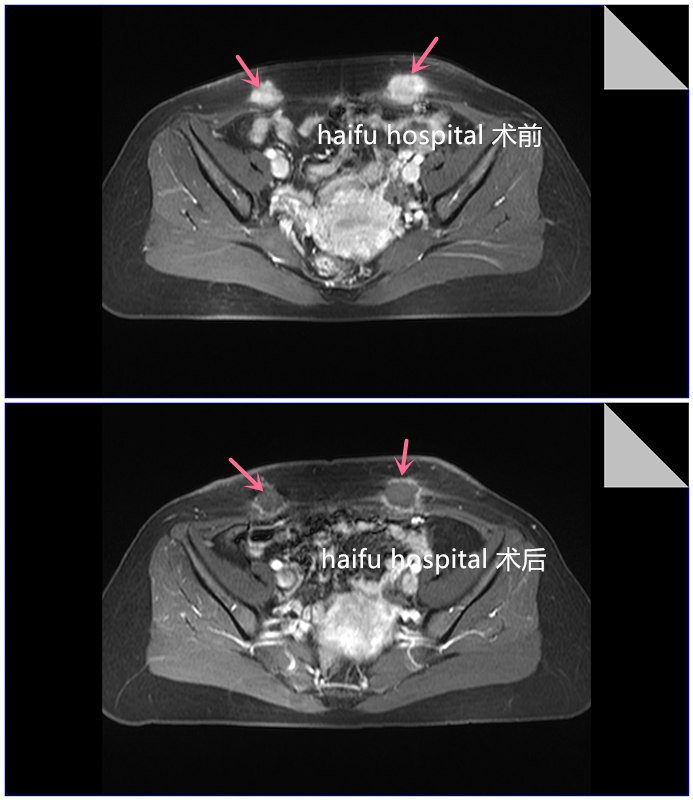

医院动态

颜女士(化名)剖宫产瘢痕左右侧有两个包块,诊断为腹壁子宫内膜异位症,随着时间推移,包块逐渐增大,并且周期性疼痛进行性加重,检查显示左侧包块约3.0cm*2.0cm,右侧约2.4cm*1.4cm,拒绝手术切除,她选择到重庆海扶医院进一步治疗。